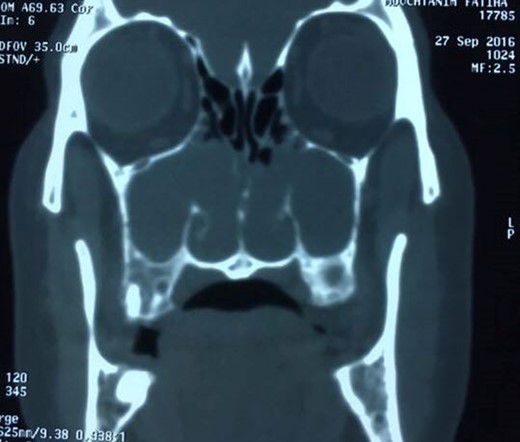

Computed tomography of the paranasal sinuses disclosed an almost complete opacification of the maxillary sinuses and the presence of a soft-tissue masses passing through the maxillary ostium and extending into the corresponding nasal cavities and posteriorly upto the nasopharynx. The other sinuses were normally aerated (Fig. 2).